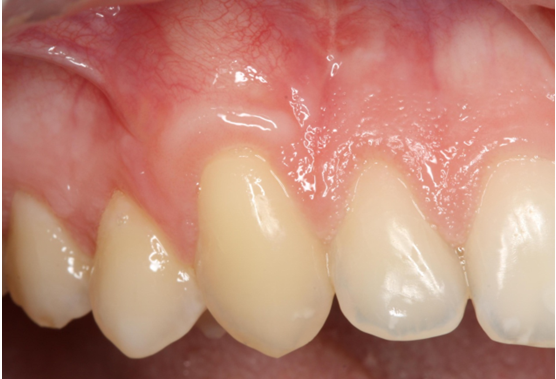

8. Κάλυψη απογυμνωμένης ρίζας

Η ασθενής εμφάνιζε προχωρημένη υποχώρηση (υφίζηση) των ούλων στον κυνόδοντα άνω δεξιά. Εφαρμόσθηκε μόσχευμα ούλων που λήφθηκε από την υπερώα και το αποτέλεσμα οδήγησε σε πλήρη κάλυψη της ρίζας του δοντιού.

Αρχική κλινική φωτογραφία

Kλινική εικόνα επούλωσης τρεις μήνες αργότερα